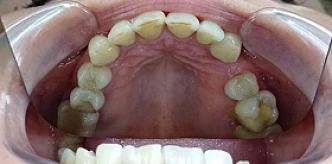

Ольга

до